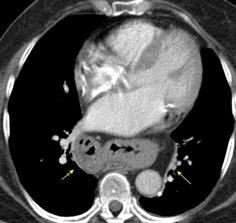

T. mixto de células germinales del testículo izquierdo

Nódulos pulmonares múltiples. (flechas verdes). Masas paratraqueales. (flechas amarillas). Dudoso ensanchamiento retrocrural (flechas negras). sigue….

Ttawfik A et al. Trans-diaphragmatic Pathologies: Anatomical Background and Spread of Disease on cross-sectional Imaging. Current Problems in Diagnostic Radiology. 2021.

T. mixto de células germinales del testículo

izquierdo Metástasis pulmonares. (flechas verdes). Ganglios paratraqueales. (flechas amarillas). Ganglios retroperitoneales (flechas negras)

Tawfik A et al. Trans-diaphragmatic Pathologies: Anatomical Background and Spread of Disease on cross-sectional Imaging. Current Problems in Diagnostic Radiology. 2021.